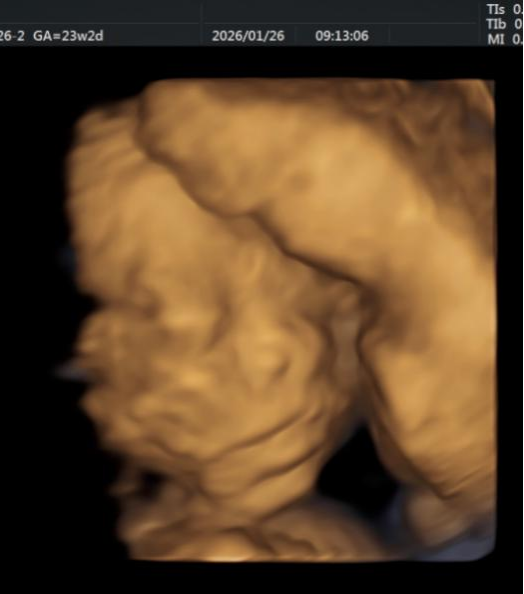

1、胎儿系统筛查

用超声之“窗”,细致探察宫内宝宝成长的每一个阶段,以专业守护新生。从孕早期的NT筛查,到孕中期的系统畸形排查,再到孕晚期的生长发育评估,超声医学科已构建起覆盖全孕周期的胎儿健康监测体系。